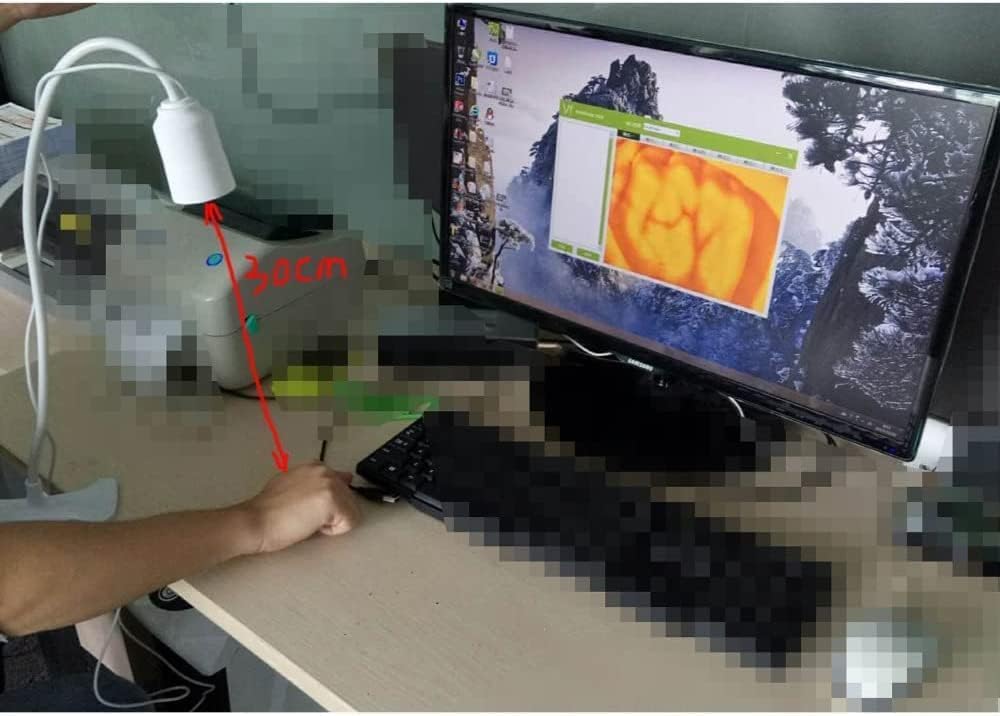

Our medical vein finder device adopts the principles of hemoglobin strong absorption of infrared light,

designed the helpful vein finder device, which consists of infrared vein collector & vein recognition system

Product volume: 25.0 cm 15.0 cm 10.0 cm

Infrared high-sensitivity 1/4inch CMOS